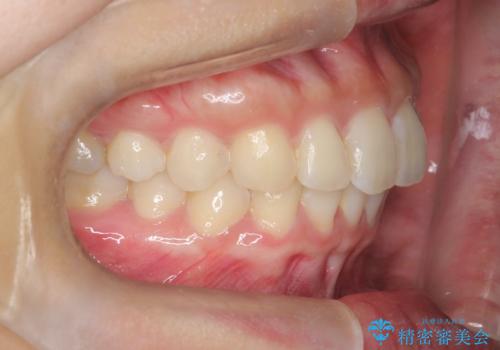

【インビザライン】翼状捻転+出っ歯を治したい

- 前歯の捻れと口元の突出を主訴に来院されました。

インビザラインを用いて上顎の遠心移動を行い、前歯を下げながら凸凹を綺麗に治すことができました。

歯を抜かない矯正治療を行う場合、口元は極端には変わりません。

今回は奥歯の遠心移動を行い、できる限り前歯を下げられるように治療を行いました。